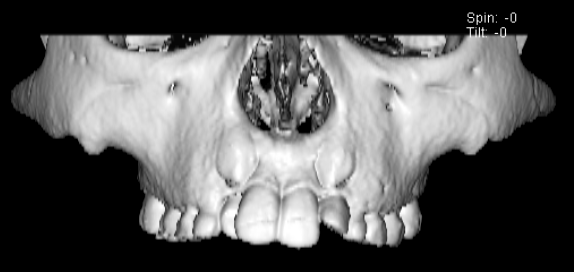

FX(フェイシャルアキシス)は85度なので東洋人の平均値に近く、下顎が前方に過剰成長するリスクは強くはありません。

しかしやはり上顎は劣成長で、下顎が優位な状態ではあります。

上下顎のギャップはありますが、顔面自体の幅径は良好な値を示していますので、スペース不足は拡大することによって解決できポテンシャルはあると考えられます。

左右の非対称もさほど強くありません。

骨年齢は実年齢よりも低めなので、今後下顎の旺盛な成長が見込まれます。